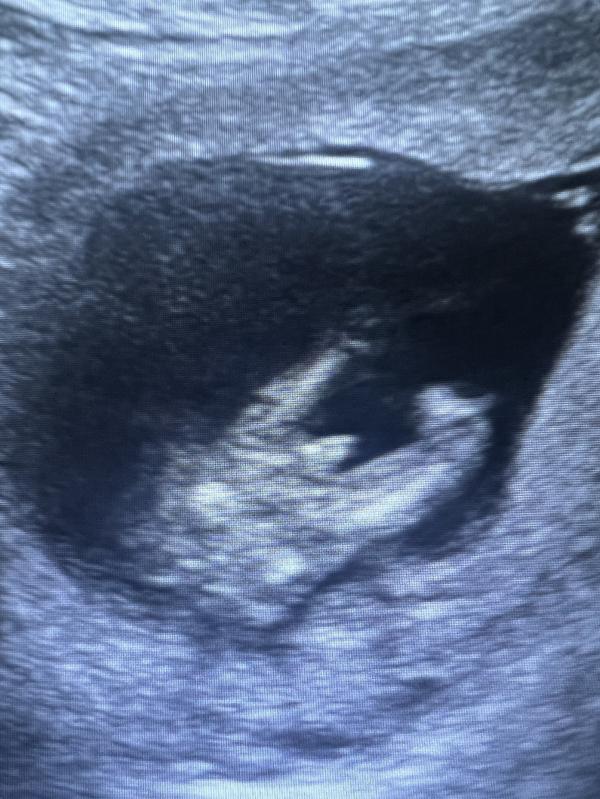

Третий сын. ❤️ ну что ж, Всевышнему виднее. Эта беременность прям отличалась и все вокруг говорили, что девочка будет. Внушила себе тоже 😅 в итоге сегодня перестраиваюсь на «мама троих мальчиков». Главное, что наш и здоров. Ждем тебя! 🥰

Подскажите пожалуйста Это узи на 12 неделе? Прям такой большой 👍у меня сегодня сказали не ярко выражен половой орган но заострен поэтому скорее всего девочка, а может быть пацан 🤣 я теперь в недоумении хотела пацана?

13 недель и 4 дня. Не знаю, многие пишут, что на этом сроке у них одинаковое. Более информативно с 16 недели. Поэтому думаю, у вас и вовсе рано, что-то увидеть.

Мне на 3 мальчика точно такое же фото сделали🤣 сказали успокойся, это мальчик😂😂😂

У меня в 13 недель на дочу сказали мальчик. 100 процентов. Я все настроилась на мальчика. И на 21 неделе говорят девочка, я в шоке

Тоже осталась малюсенькая надежда на ошибку. Но блин, она там со всех ракурсов показала, типа точно мальчик, и первый узист тоже уверенно на мальчика указала. 🙈а вам прям по узи прям показывали, что мальчик?)

До 16-17 недель у мальчиков и у девочек пол.органы почти одинаково выглядит. Поэтому есть еще шанс😀

Да, она там прям угол наклона полового бугорка показала, там уверено вверх, 90гр, что означает мальчик 😅

@aik01, ой, вообще смотря первый скрининг, можно с уверенность сказать, что у меня девочка, там бугорок меньше 30 градусов. Другой узист уже смотрела, он прямой практически. Поэтому кто как смотрит, как ребенок лежит, с какого ракурса смотреть

Ой какой большой писюнчик 😅✊🏻💪🏻 поздравляю вас

Я вас поздравляю 🙌🏻 а так можно в 13 недель увидеть уже пол ребенка?

Спасибо! 🌹 Говорят с уверенностью, что уже можно. Искала по отзывам грамотного узиста. Да, и на скрининге тоже мальчика предположили